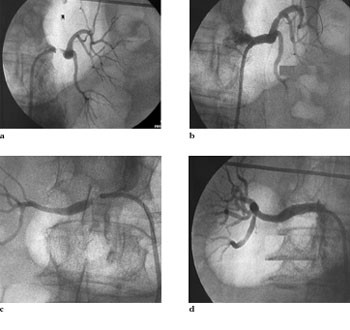

Figur 1 viser et eksempel på renal angioplastikk ved typisk fibromuskulær dysplasi. Figur 2 viser en bilateral subtotal arteriosklerotisk nyrearteriestenose før og etter angioplastikk. Vellykket initial revaskularisering og godt akutt resultat av alle stenosene hos pasienten ble oppnådd hos 92 %, mens det hos ytterligere 4 % ble oppnådd bedring. Det var 14 (5 %) mislykkede forsøk hos pasienter med arteriosklerotisk sykdom. En pasient med fibromuskulær dysplasi måtte opereres neste dag pga. mislykket prosedyre. Det var fem mislykkede forsøk hos de transplanterte (7 %). Før bruk av stent forelå det en høy restenoserate, særlig for ostiale stenoser (39 % restenose), men sluttresultatet kunne bedres betydelig ved å gjenta utblokkingen (tab 1). Segmentalgrener og små arterier med diameter< 5 mm kom dårligst ut. Pasienter med fibromuskulær dysplasi kom bedre ut enn de øvrige pasientene.